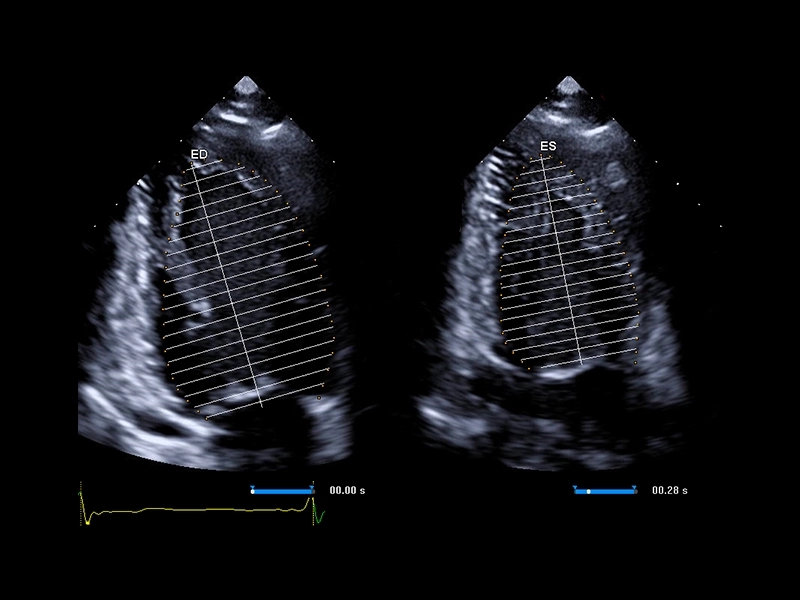

MyLab™A70 - AutoEF

MyLab™A70 - AutoEF